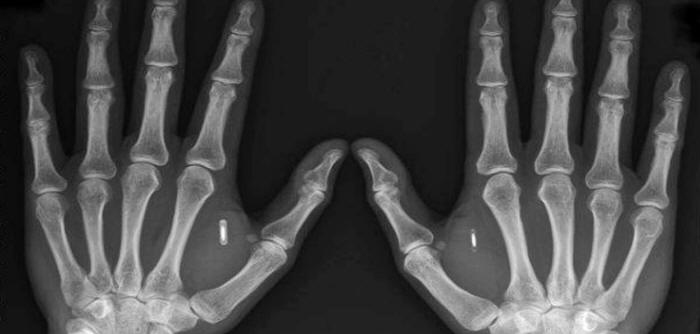

X-ray image of Two

Hands with implants.

Source:

Corrado

Malanga

(21)

Corrado Malanga Archives - According to

Malanga these would be alien

implants - Complete

PDF here.